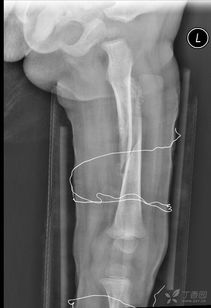

我們知道,這些微量元素是形成和發(fā)育骨骼的重要成分。另外在治療期間可以進行物理方面的治療與護理,如按摩,讓患處的血液循環(huán)變得好起來,這對于打著鋼板的患處是很有好處的,預(yù)防因長時間不活動導(dǎo)致的肌肉萎縮現(xiàn)象的發(fā)生。